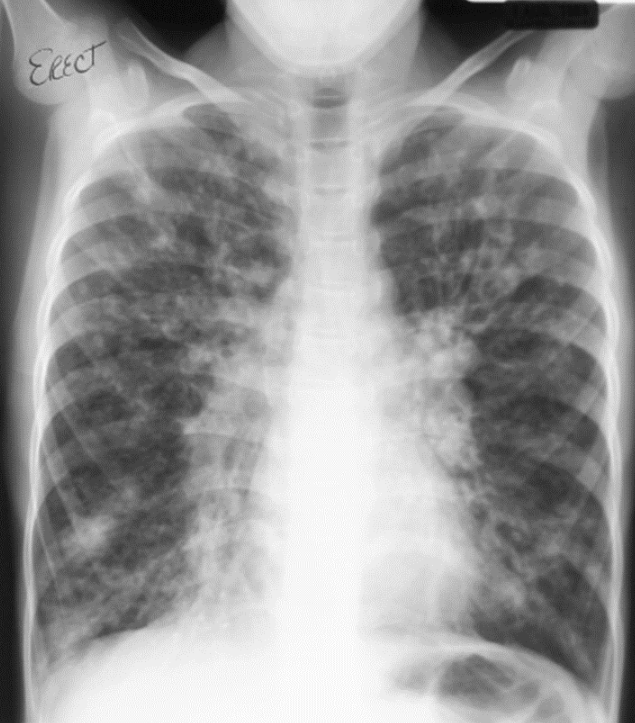

19

Q

?

A

CYSTIC FIBROSIS

-Hyperinflation (early)

-Peribronchial cuffing

-Mucous plugging

-Bronchiectasis (ring shadows,cysts)

-Increased interstitial markings

-Small rounded peripheral opacities

-Focal atelectasis

-Pneumothorax